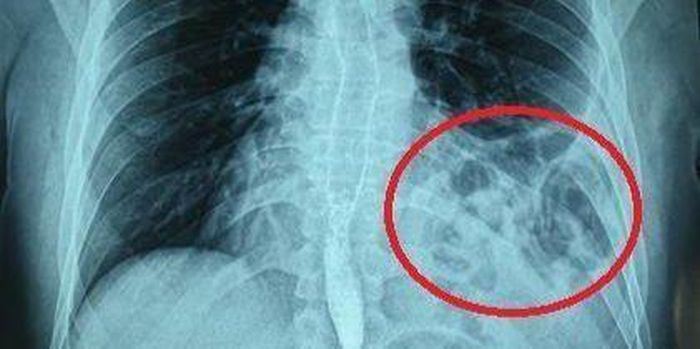

Phim X-quang cho thấy bóng khí của đại tràng ở trên ngực trái bệnh nhân. Ảnh: BV.

Tại đây, bệnh nhân đã được chỉ định chụp X-quang ngực và phát hiện có hình bóng hơi của ruột ở trên ngực trái. Bệnh nhân được hoàn thiện thêm các xét nghiệm cận lâm sàng và hội chẩn thêm các chuyên khoa, chụp cắt lớp khẳng định có thoát vị tạng bụng qua cơ hoành lên ngực trái.